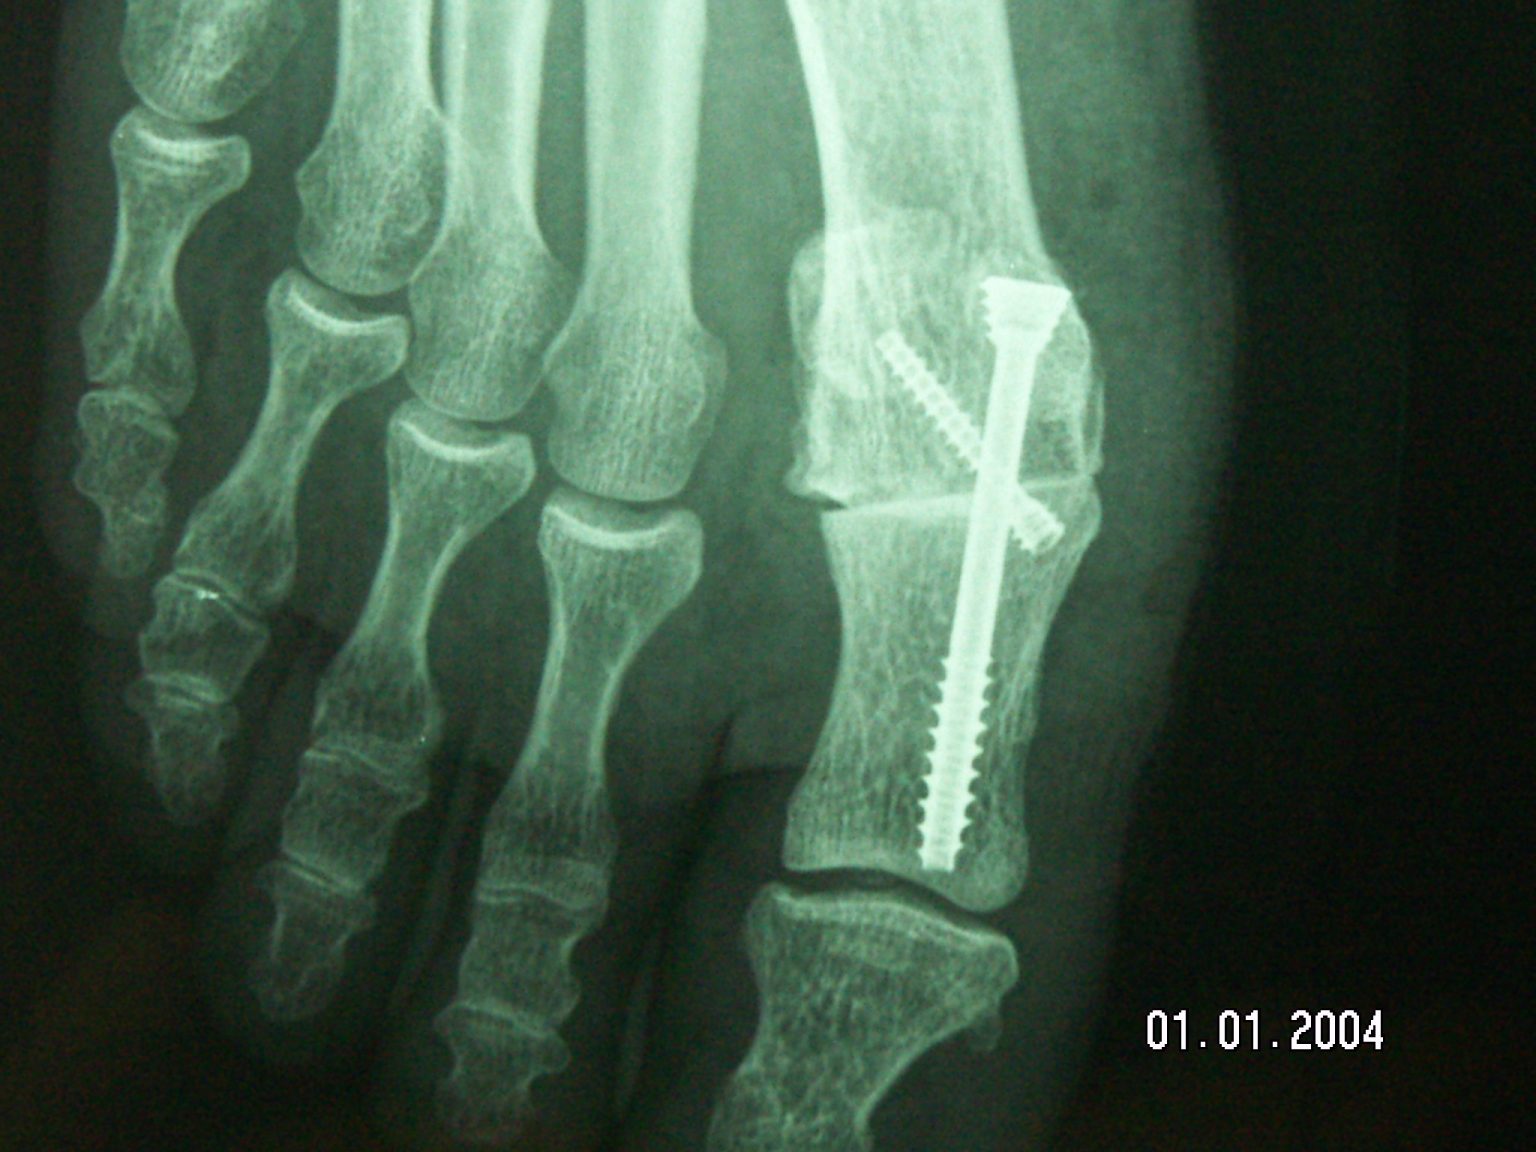

WebTraitements : des séances de kinésithérapie à la prothèse de cheville. Comme pour toutes les autres formes arthroses, l’arthrose du pied ne se guérit pas. Pourtant, elle. WebLa marche avec une arthrodèse de cheville . Contenu modifié le 25/04/17. Voir toutes les Vidéos. Centre de Chirurgie du Pied et de la Cheville 25 rue de Flesselies. WebL'arthrodèse se réfère au raidissement chirurgical d'une articulation, par lequel sa capacité naturelle à bouger est désactivée. C'est une thérapie courante pour le traitement des. WebLe kinésithérapeute du service vous montrera les exercices actifs à pratiquer chez vous. Un document expliquant les mouvements autorisés vous sera remis avec votre dossier pré. WebLes troubles de la marche englobent un grand nombre de problématiques, comprenant le ralentissement de la vitesse de marche et la perte de fluidité de celle-ci, et la perte de la. WebL’arthrodèse du premier métatarsien est une intervention fréquente, corrigeant soit des déformations, soit des destructions articulaires permettant de. WebLes sports nécessitant un contact sol pied (tennis, ski, golf, randonnée…) seront possible à partir du sixième mois. Après une arthrodèse de cheville, la cheville ne bouge plus mais. Web1 - Arthrose du pied : elle peut être due à un mauvais chaussage. 2 - Arthrose : certaines chaussures sont à éviter (et ce ne sont pas celles que vous croyez) 3 -.

Viral hallux rigidus ou arthrose métatarsophalangienne du gros orteil viral

Voyons Chirurgie sur Dunkerque, hallux rigidus

Dernier hallux rigidus ou arthrose métatarsophalangienne du gros orteil Dernier